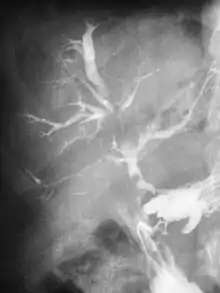

Fistula

Abdominal CT scan with right colocutaneous fistula and associated subcutaneous pneumatosis